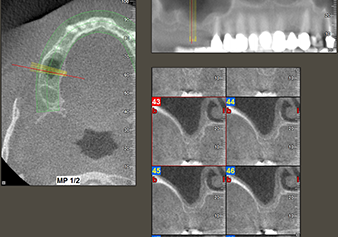

Following an intermediate check (Fig. 4) a further preparation step was performed (Fig. 5). Afterwards, the hydraulic Z35P instrument was used to lift the membrane to the desired position (Fig. 6 and 7). This was followed by further piezosurgical preparation of the implant bed, concluded with a rotary bur and shoulder milling cutter up to the implant diameter of 4.8 mm. Before the implant was inserted, the augmentation material (particle size approx. 0.8-1.6 mm) was introduced underneath the Schneiderian membrane (Fig. 8).